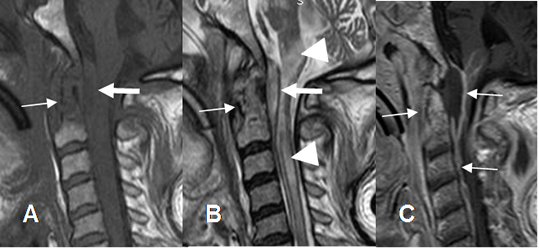

Fig 142 A. Empiema epidural.

A: RM sagital en T2, B: RM sagital en STIR y C: RM axial en T2. Espondilodisquitis C4-C5, con disminución del espacio intervertebral. Se encuentra colección epidural entre C2 y C5 que comprime el saco dural (Flechas delgadas) y prevertebral (Flechas gruesas). Adicionalmente hay hiperintensidad medular, por mielopatía secundaria. (Puntas de flecha).

Fig 142 B. Empiema epidural.

A: RM sagital en T1 simple, B: RM sagital en T1 y C: RM axial en T1 con contraste. Igual paciente anterior. Espondilodisquitis C4-C5, con colección epidural cuyos bordes realzan con el contraste y comprime el saco dural.